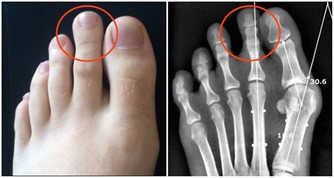

即:零死角預防、零隱患遺漏。一是指通過飲食、習慣、心態、運動等全方位預防,不留死角;二是指通過體檢、早期症狀(咯血、胸痛、咳嗽、肺外症狀:骨關節病變、異位內分泌綜合症零隱患檢查,無遺漏。